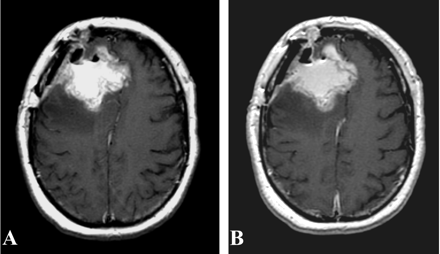

Both patients underwent IMRI-guided resection of their tumors. Preoperative MR imaging demonstrated the targeted lesion. Intraoperative MR without gadolinium, following the prior administration of ferumoxtran-10, easily provided images that demonstrated the lesions seen on preoperative MR images obtained in both patient 1 (Fig 1) and patient 2 (Fig 2). In one operation, post-resection imaging revealed a persistently enhancing area that was then resected (Fig 3). Even in the low-field-strength IMRI system, ferumoxtran-10 provided adequate imaging of the lesions in both of these patients. Postoperative MR images obtained in both patients had no significant enhancement with gadolinium, which suggests resection of the enhancing tumor bulk (Figs 4 and 5). Both postoperative MRIs show high T1 signal intensity in the wall of the resection cavity. The walls of the cavities, however, do not appear to enhance significantly with gadolinium. Figure 5 also shows the resection cavity itself filled with T1 hyperintense material. The cause of this residual T1 hyperintensity, either from blood or ferumoxtran, is unclear. Iron staining of one patient’s lesion demonstrated iron accumulation within peritumoral reactive cells (Fig 6).

Preoperative gadolinium-enhanced (A), ferumoxtran-10-enhanced (B), and intraoperative ferumoxtran-10-enhanced T1-weighted MR images (C) with arrow pointing to the enhancing lesion from patient 1. Panels B and C were obtained approximately 24 hours after ferumoxtran-10 administration.